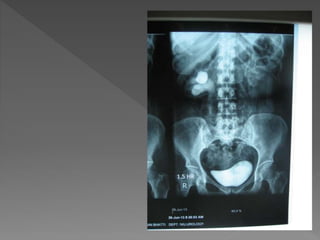

 The plain film demonstrates

 The plainfilm demonstrates calcification within distended upper pole calyces